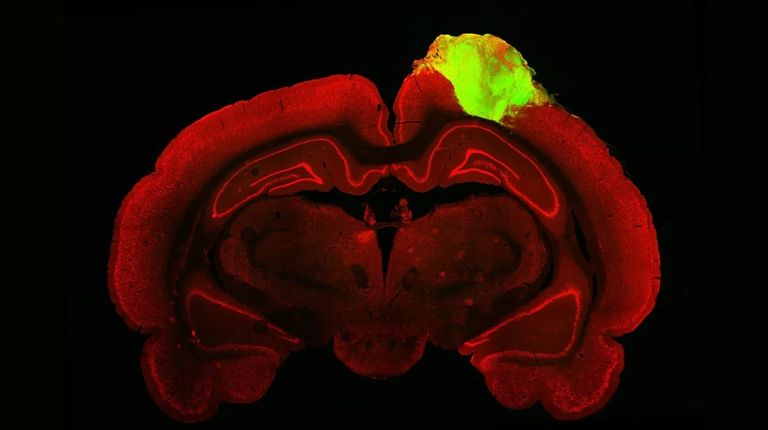

وذكرت الصحيفة أنه تم استخدامها لأول مرة في عام 2013 لفحص صغر الرأس، وهي حالة يكون فيها رأس الرضيع أصغر بكثير من المتوسط، ومنذ ذلك الحين تم استخدام نقط الدماغ لدراسة أمراض مثل ألزهايمر، وباركنسون، وزيكا، وإصلاح أدمغة الفئران المصابة بطعوم في وضع جيد.